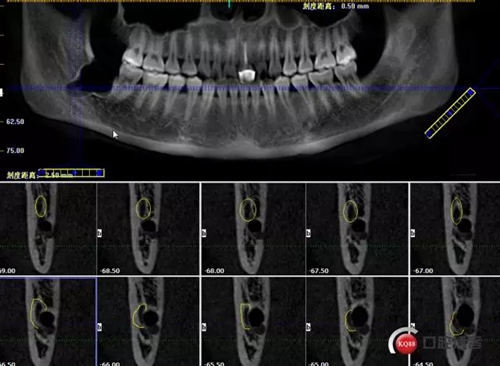

術(shù)前曲面斷層

1498615723_447506.png

牙齒上1/3CT切片,神經(jīng)管在下方